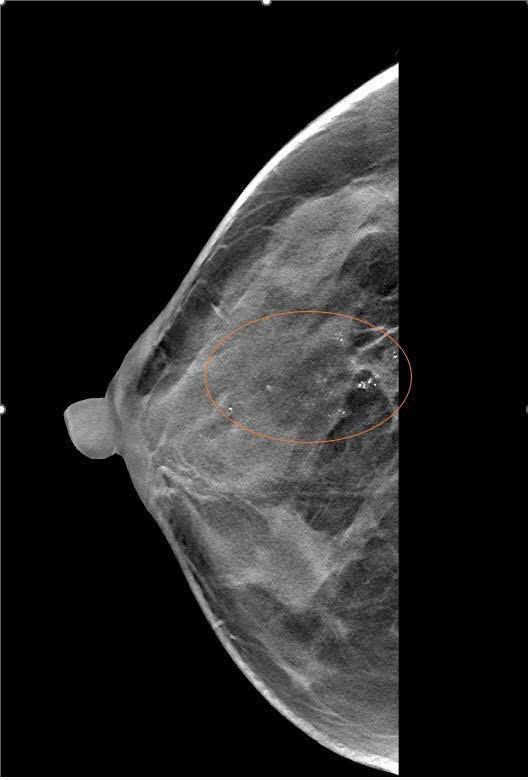

XQUANG VÚ 3D tại Mammocare: Chất Lượng Cao, Công Nghệ Hiện Đại với Máy Mammomat Inspiration

Ung thư vú là một trong những bệnh lý nguy hiểm nhưng hoàn toàn có thể chữa khỏi nếu được phát hiện sớm. Một trong những công cụ tầm soát hiệu...